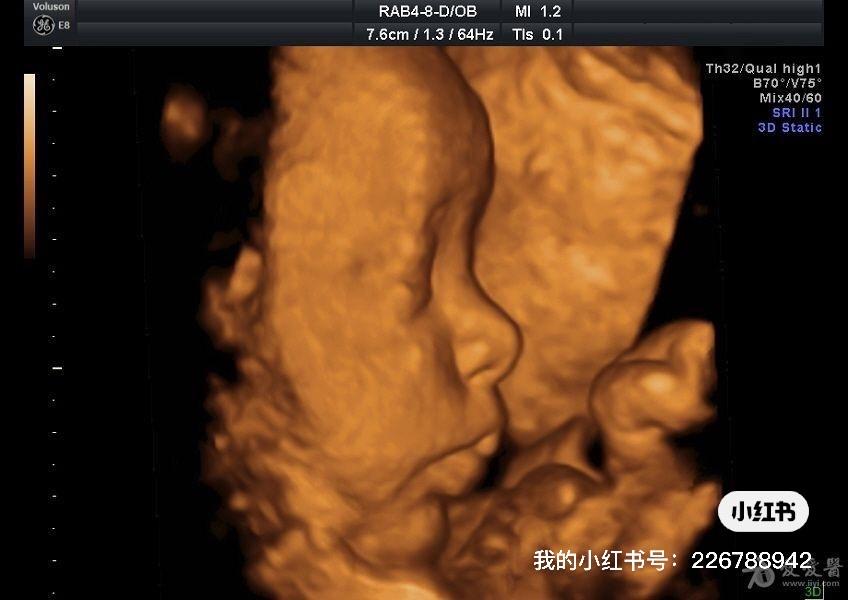

昨天我们讲到了传说中的三维超声,在私立医院的宣传手册上被描绘成“与宝宝跨越时空的约会”。三维超声有这么准确,有这么神奇吗?今天我们就来聊一聊。

三维超声在保留二维成像的基础上进行立体定位、图像切割、图像旋转及高平面图像分析,从而立体直观地观察胎儿头部、躯体表面及内脏活动,显示结构不同层次的立体关系及毗邻关系。它的优势在于可以进一步评估实时灰阶二维超声中的不确定结果,或提供标准灰阶超声所不能检测的更广泛评估。胎儿三维超声的表面成像模式可以更好显示之前由二维超声检出的异常,尤其是面部、骨骼和中枢神经系统的异常。

而四维超声检查–四维超声又称动态三维超声,是指可实时观察动态的三维成像。现已用于检查胎心、胎动和胎儿行为状态。